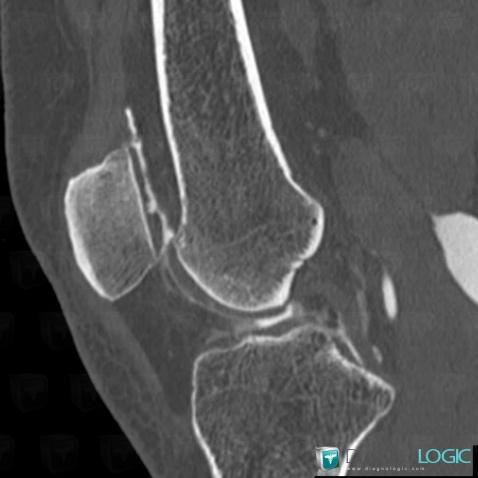

Degenerative joint disease, Patellofemoral joint, CT

Here is the specific information in the key image above:

- Diagnosis Degenerative joint disease, Location(s) Patellofemoral joint, with gamuts